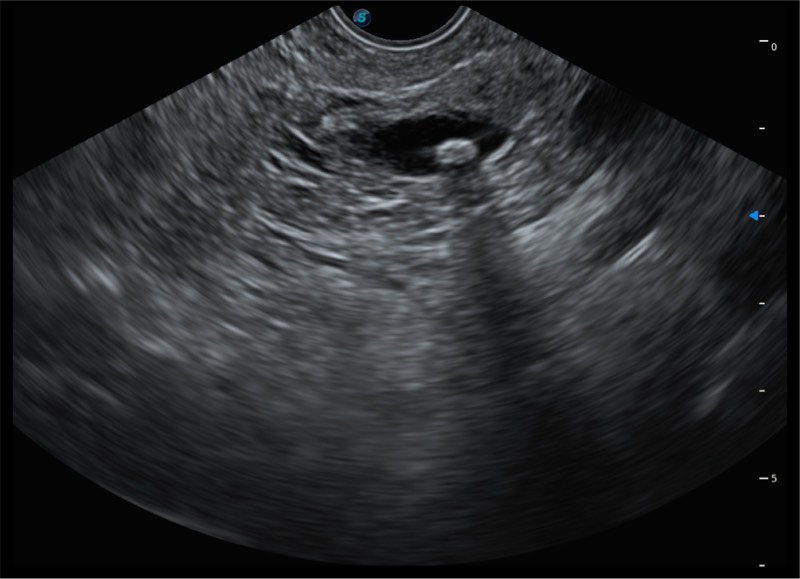

12.6mm先端部外径

150°超声扫描角度